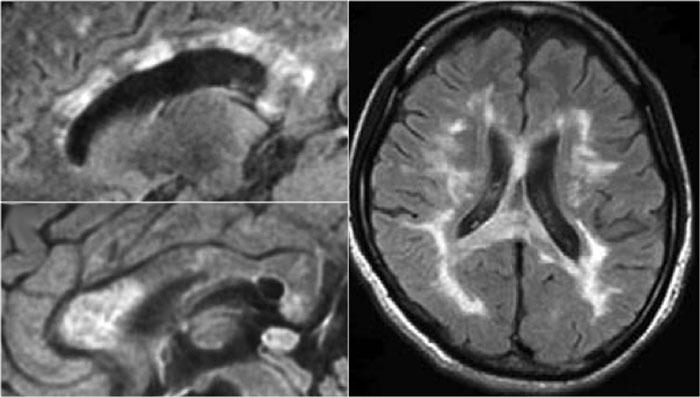

Viêm Tủy Thị Thần Kinh (Neuromyelitis Optica)

NMO biểu hiện với viêm thần kinh thị giác (mũi tên). Não bình thường. Hình ảnh cung cấp bởi Andrea Rossi

Hình ảnh bên trái của một trẻ em nhập viện với viêm thần kinh thị giác một bên.

Hình ảnh não hoàn toàn bình thường.

Tiếp tục xem MRI cột sống.

Những bệnh nhân có một đợt viêm thần kinh thị giác hoặc viêm tủy và có kết quả xét nghiệm NMO-IgG dương tính có nguy cơ cao tiến triển thành toàn bộ phổ bệnh NMO.

Một tháng sau, trẻ này nhập viện với bệnh tủy cắt ngang cấp tính, tức là các triệu chứng hai bên.

Hình ảnh cho thấy tín hiệu bất thường trong tủy sống kèm phù nề và ngấm thuốc nhẹ.

U tế bào hình sao (astrocytoma) hoàn toàn có thể biểu hiện với hình ảnh tương tự, tuy nhiên dựa vào tiền sử viêm thần kinh thị giác và bệnh tủy cấp tính, chúng ta không nghĩ đến khối u.

Trường hợp này được xác định là NMO và xét nghiệm Ig cho NMO dương tính.

Tổn thương não trong NMO

Trước đây người ta cho rằng não không bị ảnh hưởng trong NMO, nhưng hiện nay chúng ta biết rằng các tổn thương não có thể xảy ra.

Chúng thường khác biệt so với các tổn thương thấy trong MS.

Tại châu Á, 60-80% bệnh nhân NMO có bất thường trên não.

Tại châu Âu, tỷ lệ này chỉ là 25-40%.

Vị trí của các tổn thương não trong NMO chỉ nằm xung quanh các não thất.

Lý do tại sao các tổn thương não này nằm xung quanh các não thất như sau:

Các tự kháng thể NMO IgG nhắm vào các kênh nước Aquaporin-4.

Tương tự như các kênh natri và kali trong tế bào, cũng tồn tại các kênh nước.

Nồng độ cao nhất của các kênh nước Aquaporin-4 được tìm thấy xung quanh các não thất.

Hình ảnh cho thấy tín hiệu bất thường xung quanh não thất ba và sừng trán của các não thất bên.

Vấn đề trở nên phức tạp hơn khi cũng có thể gặp các tổn thương lớn ở thể chai (corpus callosum) ở bệnh nhân NMO, như đã được Nakamura mô tả (6).

Do đó, trong bất kỳ bệnh lý hệ thần kinh trung ương nào có tổn thương thần kinh thị giác và tủy sống, nên thực hiện xét nghiệm NMO-IgG.